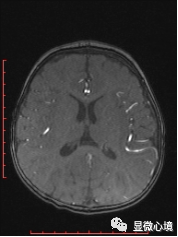

图1 SWS患儿MRI图像,左侧顶枕叶脑表面血管增粗迂曲

具体来讲,SWS是以一侧三叉神经分布区(V1/V2)不规则红斑、对侧偏瘫、偏身萎缩、同侧颅内钙化、青光眼、癫痫、智能减退为特征的先天性肌病,多为散发病例,少数有家族聚集性,发病率约20/10万。目前认为其可能的发病机制为胚胎发育5-8周时原始血管异常所致,可能涉及血管结构和功能的调控异常、神经支配异常、细胞外基质和血管活性因子的表达异常。依据其临床表现及病变受累范围,将其分为三型,即I型:经典型,有面部红斑、颅内软脑膜血管病变,可伴有眼部病变如青光眼;II型:不全型,有面部红斑、青光眼,无颅内血管病变;III型:非经典型,有颅内软脑膜血管病变,多无青光眼,无面部红斑。临床上症状性(继发性)癫痫,可表现为间断抽搐,发作时双眼向下凝视,下肢持续抖动,不伴口唇发绀、意识丧失、大小便失禁等不适,通常持续几分钟后自行缓解,发作后精神状态好。脑部核磁共振显像(MRI)可表现为病变区脑沟增宽、加深,表面血管增粗迂曲,软脑膜明显增厚强化。